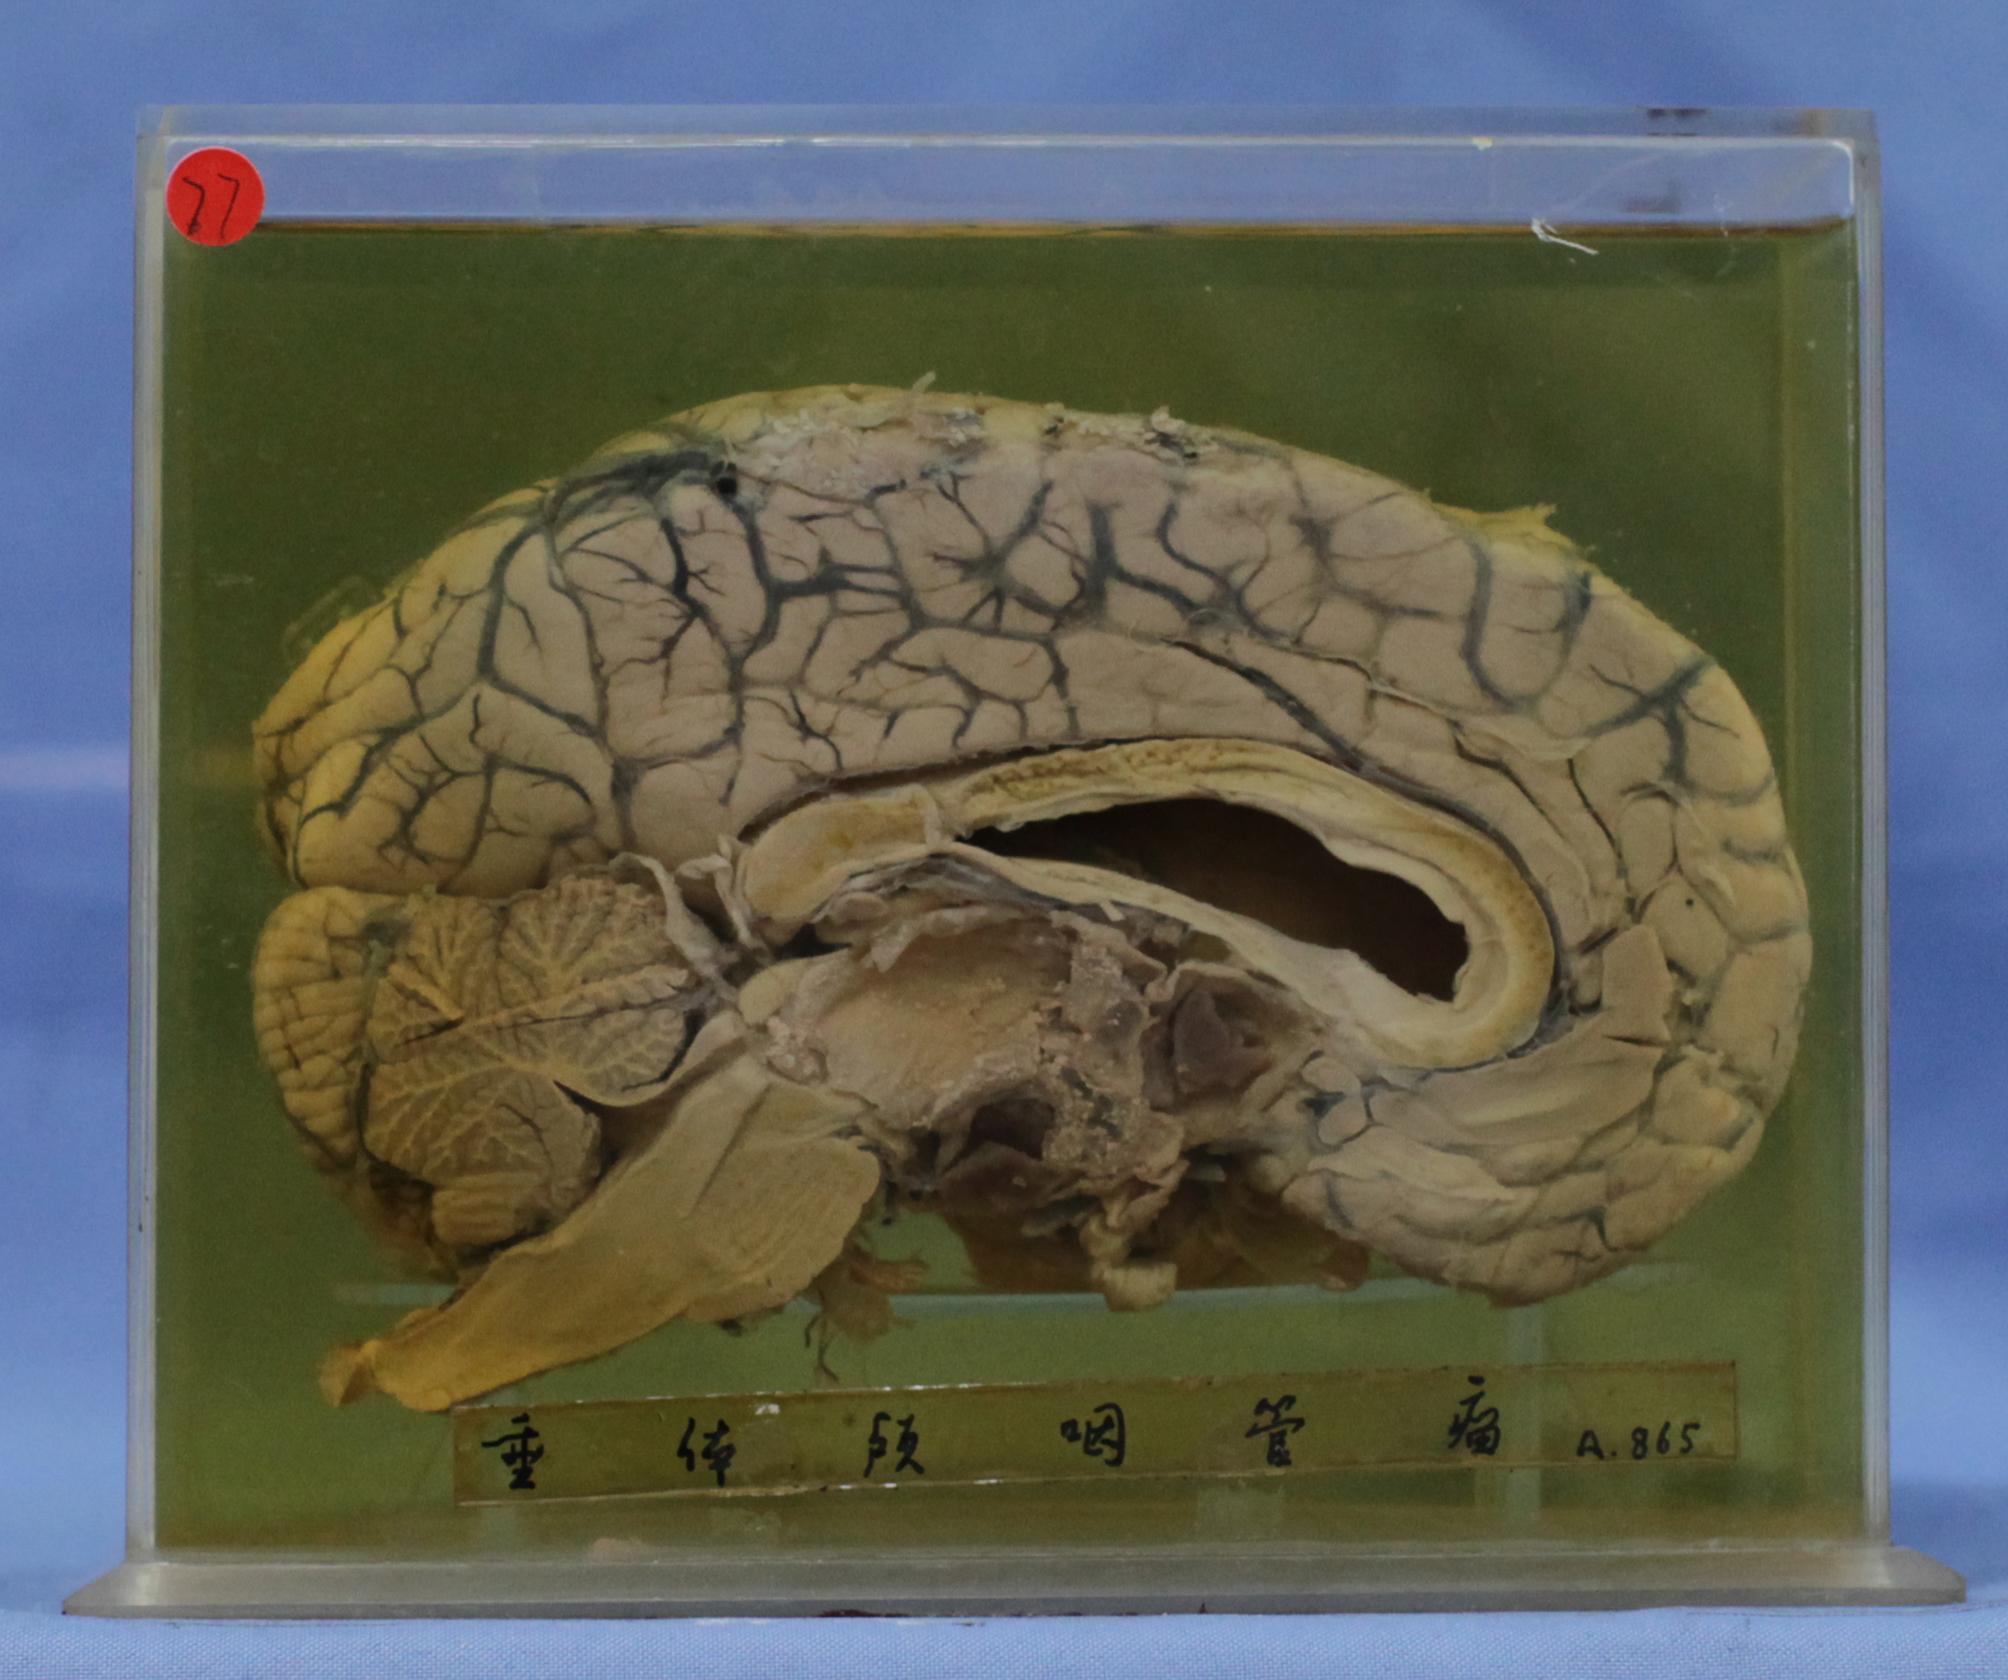

神经疾病-66-77.同76颅咽管瘤

大脑矢状切面,在鞍区附近可见2×2cm囊性肿块,其囊壁尚附有少量灰黄色坏死物质,镜检证实其为颅咽管瘤。